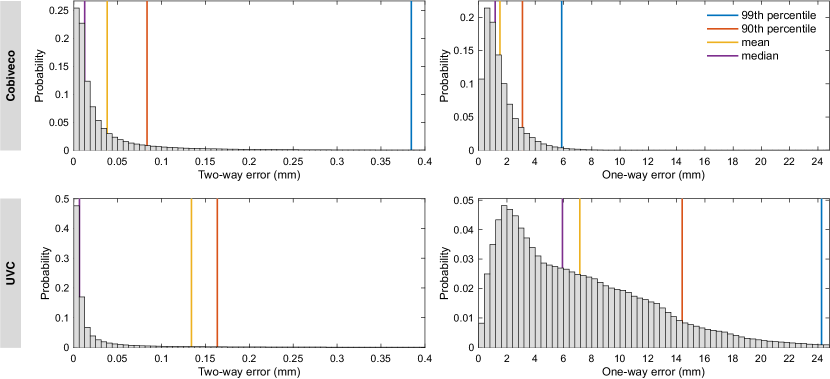

4.3 Transfer errors

The transfer errors as defined in section 3.3 were computed for all patient geometries as well as both possible directions. To condense the results, we averaged the error histograms across all geometries and both directions. This leads to an equal weighting of errors for each case, independent of the number of nodes in the respective mesh. The average histograms are depicted in Fig. 15. Statistical measures (vertical lines) of the average histograms are given in Table 1.

The two-way error shows a 3.5-fold improvement of the mean and the 99th percentile is reduced even more. However, the median is increased, which indicates that there are more small (), but fewer large errors than for UVC. With a mean value well below one mean edge length, our two-way errors for UVC are comparable to those in [2].

The one-way error is more relevant in practice as it goes beyond evaluation of interpolation errors. Here, the error histogram decays much faster for Cobiveco and all statistical measures show a more than 4-fold improvement compared to UVC. In particular, the mean one-way error is reduced from 7.1 to 1.5 mm and the 99th percentile is reduced from about 24 to 6 mm.

| Error type | Coordinate system | Median | Mean | 90th P. | 99th P. |

|---|---|---|---|---|---|

| Two-way | Cobiveco | 0.013 | 0.038 | 0.084 | 0.385 |

| UVC | 0.007 | 0.134 | 0.164 | 2.944 | |

| Improvement factor | 0.52 | 3.52 | 1.96 | 7.66 | |

| One-way | Cobiveco | 1.17 | 1.51 | 3.10 | 5.87 |

| UVC | 5.93 | 7.15 | 14.4 | 24.26 | |

| Improvement factor | 5.08 | 4.75 | 4.65 | 4.13 |